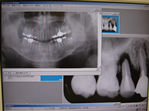

デジタルエックス線

少ない被爆線量で鮮明な画像を得られます。従来のエックス線撮影法よりもクリアな画質、撮影した画像はすぐに各ユニットモニター画面でご覧頂けます。